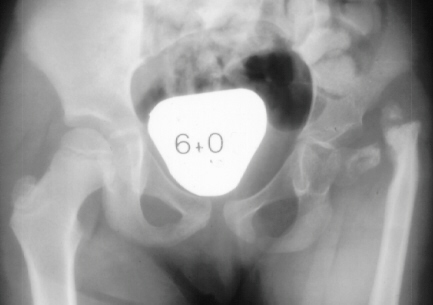

This child was 6 months old when she was referred for a second opinion on her lower extremity deformity. She was the product of a normal pregnancy and delivery. Considerable shortening of the left lower extremity was noted with abnormal musculature about the hip and a marked laxity about the knee joint. The left foot showed valgus deformity and had only four toes.